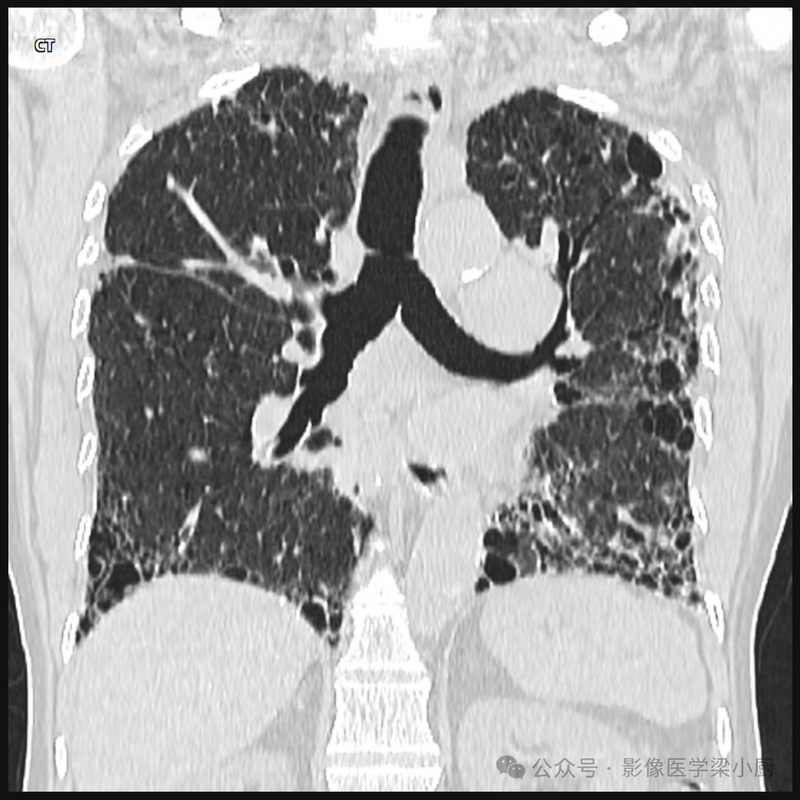

CT:

可见两侧肺野弥漫分布的网状影,以下肺野明显。HRCT可见小叶间隔及叶间胸膜增厚。有时,两肺可见多发弥漫分布的小片状或结节状影,边缘清楚或模糊。有时可见小叶肺气肿或肺不张征象。在急性间质性肺炎早期阶段,由于肺泡腔内炎症细胞浸润伴少量渗出液,肺泡内尚有一定的气体,可见磨玻璃样密度影。肺门和气管旁淋巴结可肿大。